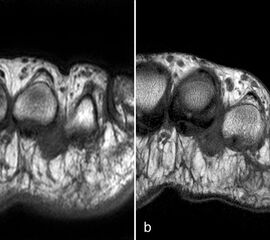

Der Begriff Morton-„Neurom“ ist im Grunde veraltet und irreführend, denn es handelt sich weder um einen Nerven- noch um einen Nervenscheidentumor, sondern um eine perineurale Fibrosierung. Da das interdigitale Gefäßnervenbündel charakteristisch in die Läsion hinein- und distal auch wieder aus der Läsion herauszieht, entsteht lediglich das Bild eines vom Nerven ausgehenden Tumors. Die charakteristischen Merkmale von Morton-„Neuromen“ sind deren Lage plantar auf Höhe der Metatarsaleköpfchen und die oft typische tropfenförmige Konfiguration (Abb. 10).

Aufgrund des hohen Bindegewebsanteils sind sie in der MRT in T2-gewichteten Bildern in der Regel auffallend signalarm, die T1 zeigt eine unspezifische Weichteilintensität. Die Anreicherung nach intravenöser Kontrastmittelgabe ist sehr variabel und erlaubt somit kaum diagnostische Rückschlüsse.

Durch seitliche Kompression des Fußes verlagern sich Morton-„Neurome“ oft weiter nach plantar in die Weichteile. Klinisch entspricht dies dem sogenannten Mulder-Zeichen 4. In der Bildgebung kann man sich den Effekt zu Nutzen machen, indem man in Bauchlage untersucht und durch die seitliche Fixierung eine entsprechende Kompression erzeugt. Die Befunde sind dann oft deutlich besser zu erkennen (Abb. 11).

Morton-„Neurome“ liegen fast immer im zweiten oder dritten Interdigitalraum. Zu beachten ist, dass Morton-„Neurome“ über lange Zeit größenkonstant sein können (Abb. 12) und kleinere Morton-„Neurome“ (unter 5 mm) sehr häufig bei asymptomatischen Gesunden beobachtet werden.